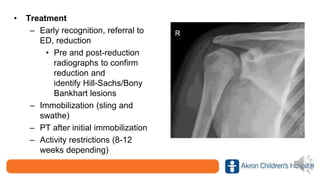

• Treatment

– Early recognition, referral to

ED, reduction

• Pre and post-reduction

radiographs to confirm

reduction and

identify Hill-Sachs/Bony

Bankhart lesions

– Immobilization (sling and

swathe)

– PT after initial immobilization

– Activity restrictions (8-12

weeks depending)

• Treatment – Earlyrecognition, referral to ED, reduction • Pre and post-reduction radiographs to confirm reduction and identify Hill-Sachs/Bony Bankhart lesions – Immobilization (sling and swathe) – PT after initial immobilization – Activity restrictions (8-12 weeks depending)